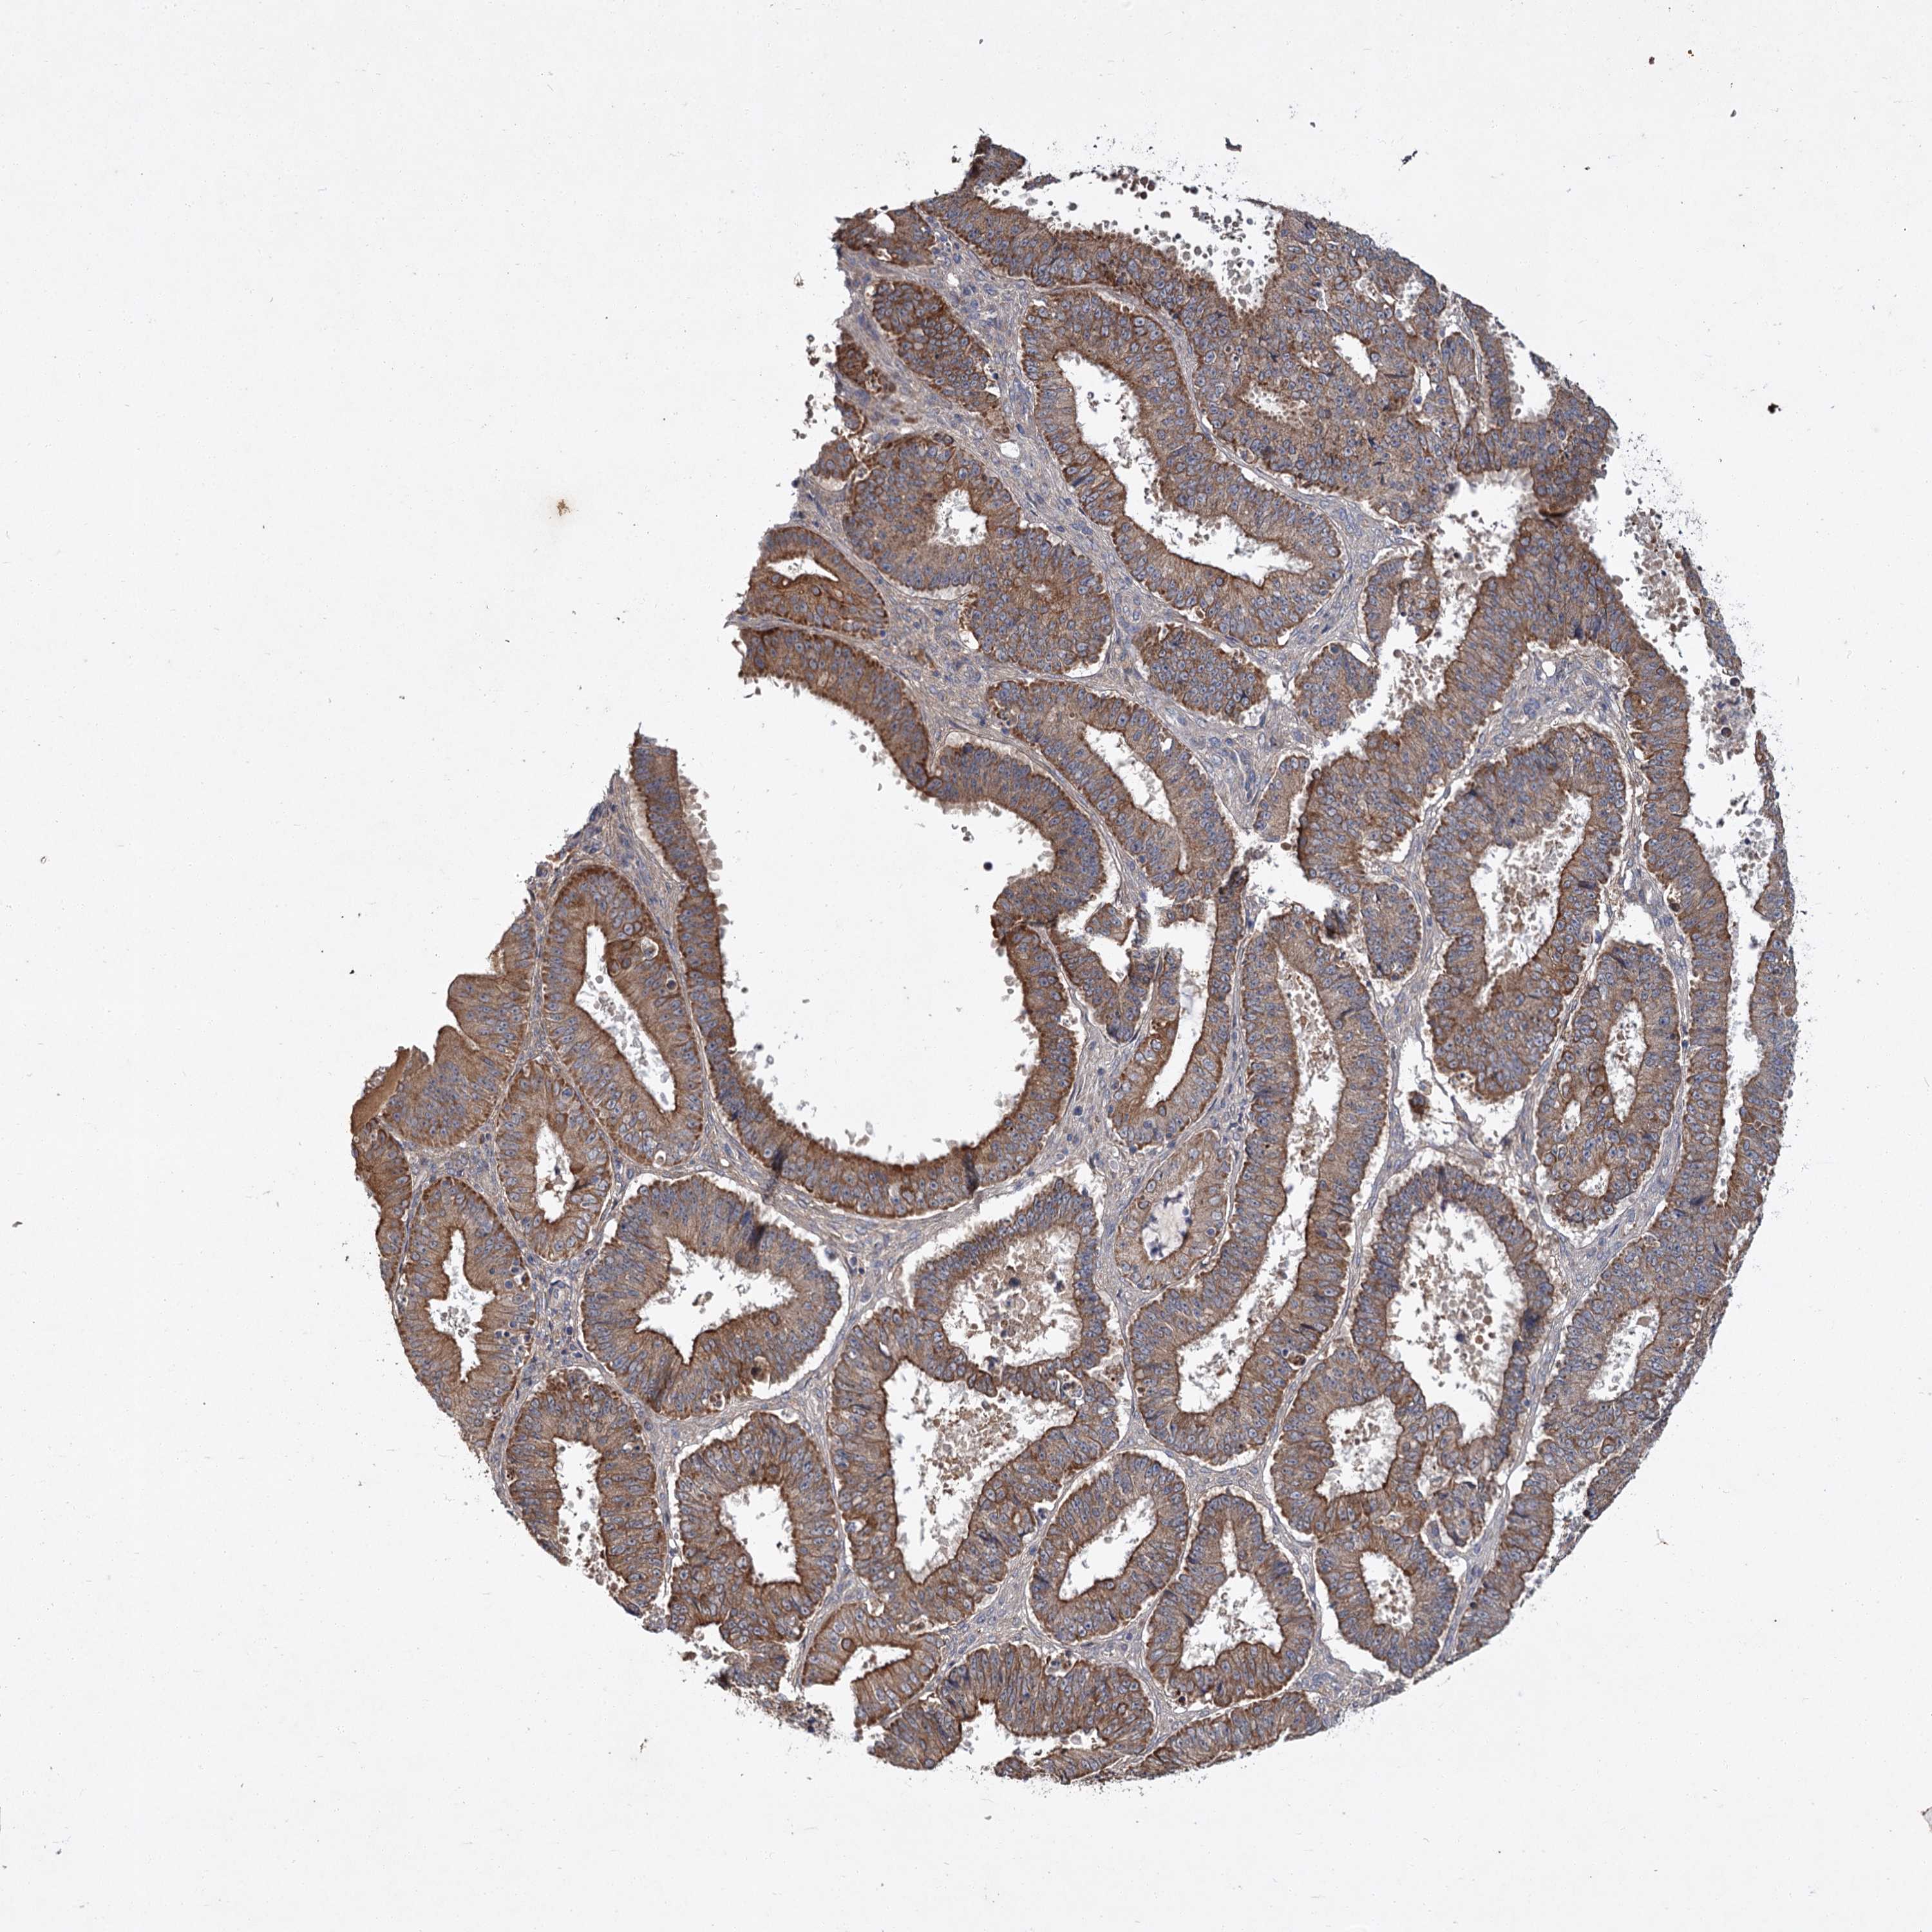

OVARIAN CANCER - Protein expressioni

A mouse-over function shows sample information and annotation data. Click on an image to view it in a full screen mode. Samples can be filtered based on level of antibody staining by selecting one or several of the following categories: high, medium, low and not detected. The assay and annotation is described here.

Note that samples used for immunohistochemistry by the Human Protein Atlas do not correspond to samples in the TCGA dataset.

Antibody stainingi

Antibody staining in the annotated cell types in the current human tissue is reported as not detected, low, medium, or high, based on conventional immunohistochemistry profiling in selected tissues. This score is based on the combination of the staining intensity and fraction of stained cells.

Each image is clickable and will lead to virtual microscopy that enables deeper exploration of all samples and also displays staining intensity scores, fraction scores and subcellular localization as well as patient and tissue information for each sample.

Antibody CAB033437

Staining

High

Medium

Low

Not detected

Intensity

Strong

Moderate

Weak

Negative

Quantity

>75%

75%-25%

<25%

None

Location

Nuclear

Cytoplasmic/membranous

Cytoplasmic/membranous,nuclear

Cystadenocarcinoma, serous, NOS

Carcinoma, endometroid

Cystadenocarcinoma, mucinous, NOS

Carcinoma, NOS